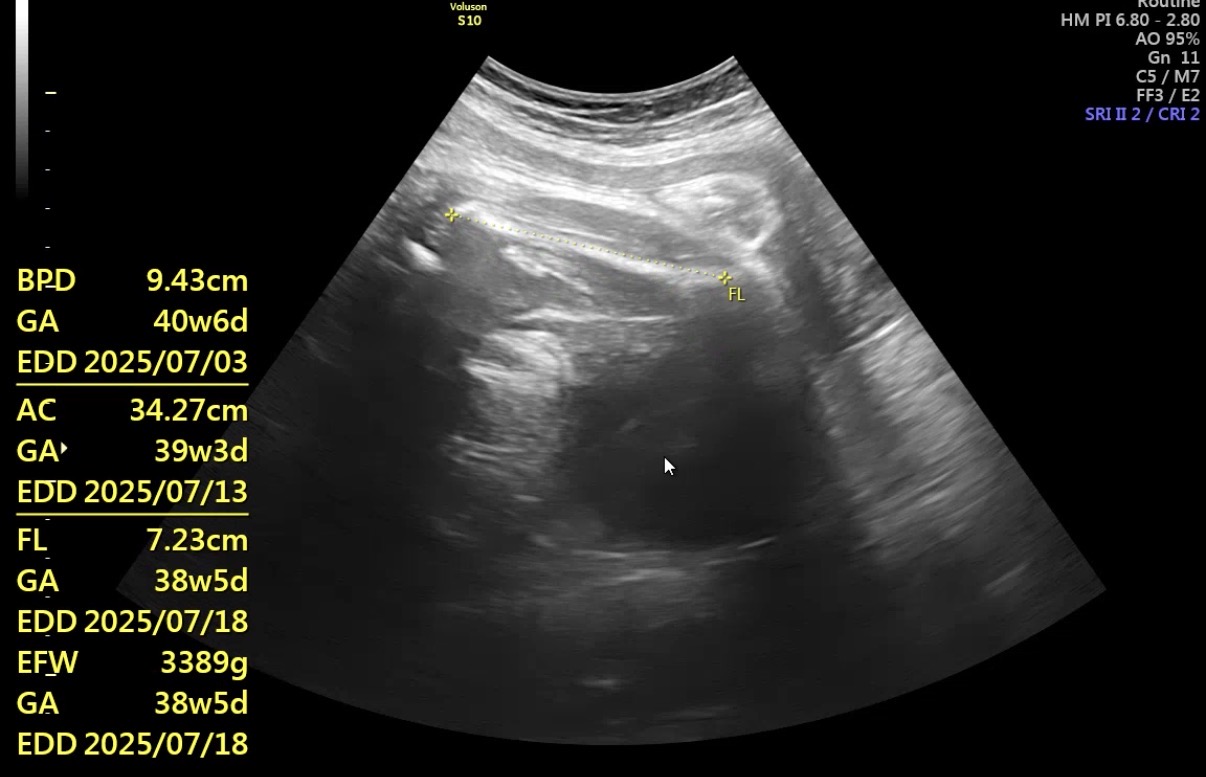

38주 3일차,

오늘 진료에서는 아기 상태를 먼저 확인하고,

머리는 아래로 내려와 있지만,

골반 안으로는 아직 충분히

내려오지 않았다는 의미라고 했다.